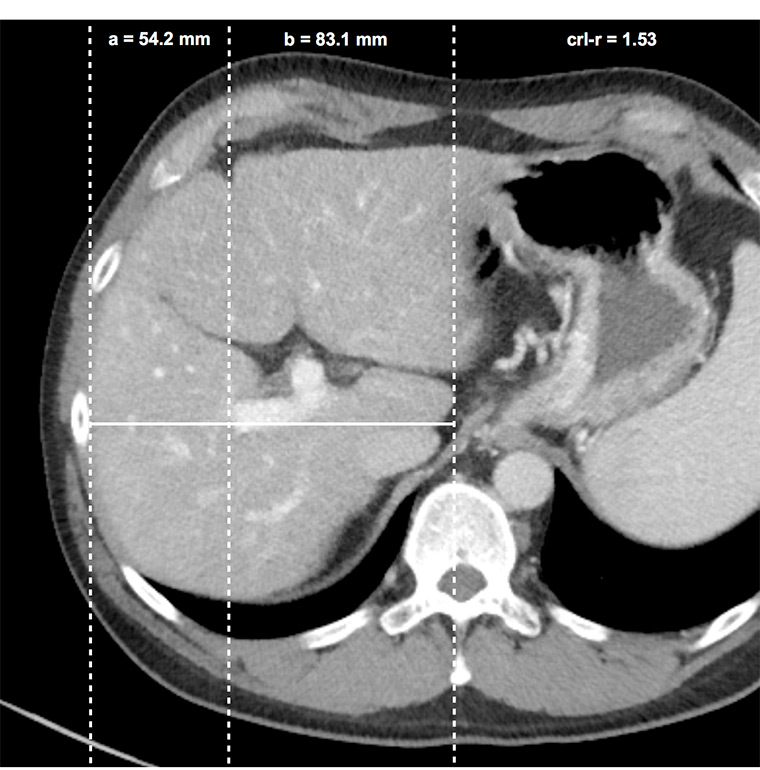

Figure 3

Caudate right-lobe ratio (crl-r) in a patient with liver fibrosis. In axial planes distances of the right lateral border of the right portal vein bifurcation to the lateral margin of the right hepatic lobe (a) and to the most medial margin of the caudate lobe (b) are measured in an exactly horizontal direction. The two distances were divided b / a (caudate lobe / right lobe) and defined as the caudate-right-lobe ratio (crl-r).

Images of all 148 patients (80 cirrhosis, 35 precirrhotic fibrosis and 33 control patients) were acquired by a 64–row-CT-unit Somatom Sensation 64 (24 x 1.2 mm, pitch 0.8, slice 1.5/5 mm, Siemens, Erlangen, Germany). Exclusively, 5-mm axial CT slices of portal-venous abdominal CT-scans were used. The scans were systematically reviewed in consensus by two radiologists with 2 and 10 years of experience in abdominal imaging, who were blinded to any clinical and imaging results or histological fibrosis stage. The diameters of the three main liver veins were measured 1–2 cm before their aperture into the inferior caval vein (fig. 2) and added to give a sum (ld-score). Accessory hepatic vein branches were not measured. The caudate-right lobe ratio (crl-r) was calculated as described by Awaya et al. [18]. Distance from the right lateral border of the first bifurcation of the right portal vein to the medial border of the caudate lobe and to the lateral border of the right liver lobe were divided as illustrated in figure 3.

The best predictor to detect liver fibrosis was a combination of the liver vein diameters and the caudate-right-lobe ratio (ld/crl-r). This ratio is calculated by adding the diameter of the three main liver veins 1–2 cm away from the inferior caval vein (fig. 2) and dividing this sum by the caudate-right lobe ratio (fig. 3).